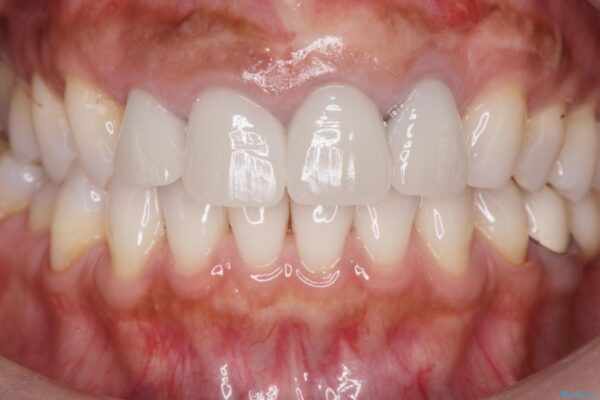

治療後

歯槽堤保存術を併用したブリッジ治療 治療後画像 歯槽堤保存術を併用したブリッジ治療 治療後画像 歯槽堤保存術を併用したブリッジ治療 治療後画像 歯槽堤保存術を併用したブリッジ治療 治療後画像 歯槽堤保存術を併用したブリッジ治療 治療後画像 歯槽堤保存術を併用したブリッジ治療 治療後画像 歯槽堤保存術を併用したブリッジ治療 治療後画像

治療を終えて

一件綺麗に見えるセラミックも適合や精度が悪いと、内部で虫歯が進行し亀裂や破折、悪臭の原因となることがあります。